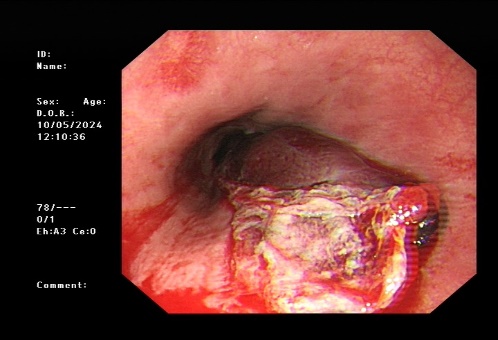

5.新疆医院多学科通力合作,成功救治一名危重症患者

5月9日,在重症医学科副主任驻疆专家王春亚、消化内科驻疆专家史海涛、心血管内科驻疆专家韩捷、麻醉科驻疆专家袁浩峥的全力协作下,成功救治一名反复呕血伴肾衰和高血压的危重症患者,体现新疆医院多学科联合救治能力。

治疗前胃镜检查结果

治疗后胃镜检查结果